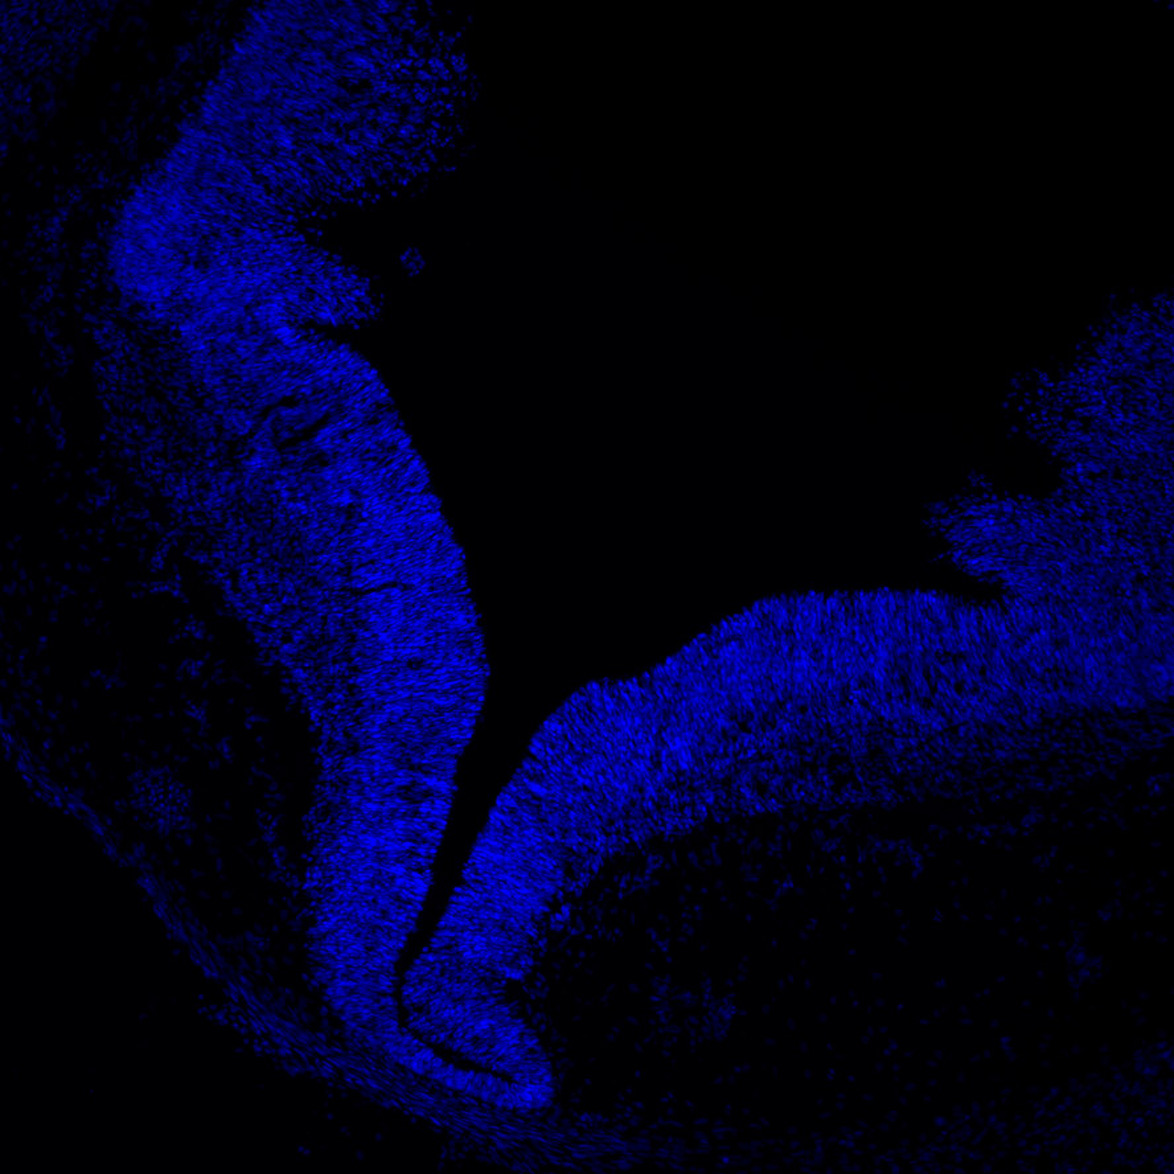

11PCW

DAPI

11PCW human midbrain